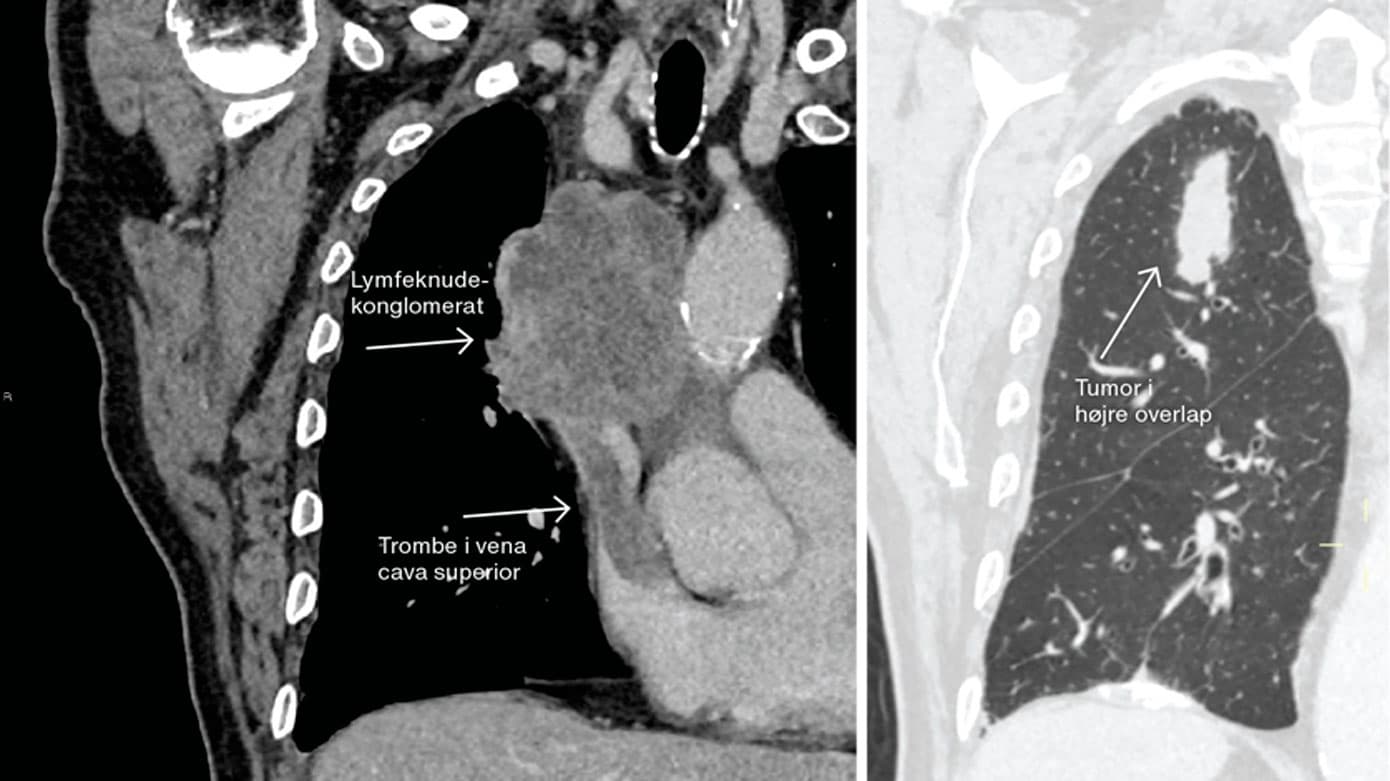

En CT af thorax viste tumor i højre øvre pulmonallap, stort mediastinalt lymfeknudekonglomerat og indvækst i vena cava superior med trombe. En histopatologisk undersøgelse viste småcellet lungecancer, og der blev indledt kemoterapi og strålebehandling.